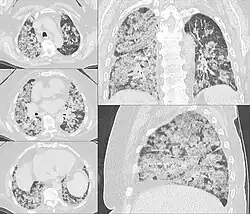

Diffuse hemorrhage from the alveoli in the lungs

Pulmonary

This commonly occurs when a distal pulmonary artery becomes occluded following a pulmonary embolism or other lung pathologies that can include malignancy, infection, or vasculitis. A large percentage (77%- 87%) of lung infarctions occur unilaterally, and typically in the lower lobes compared to the upper lobes. Symptoms of pulmonary infarction and pulmonary embolism are similar. Dyspnea, chest pain, pain and swelling in a lower extremity, and hemoptysis are common symptoms in both. Chest X-Ray can demonstrate a "Hampton's Hump" when pulmonary infarction is present, but Cat Scan is more commonly used. Treatment is dictated by the underlying cause of the pulmonary infarction which has a broad differential diagnosis that should be considered during treatment. The underlying cause will assist in a treatment plan to include level of care during initial management and the involvement of various specialists as pulmonary infarction can be deadly.[6]